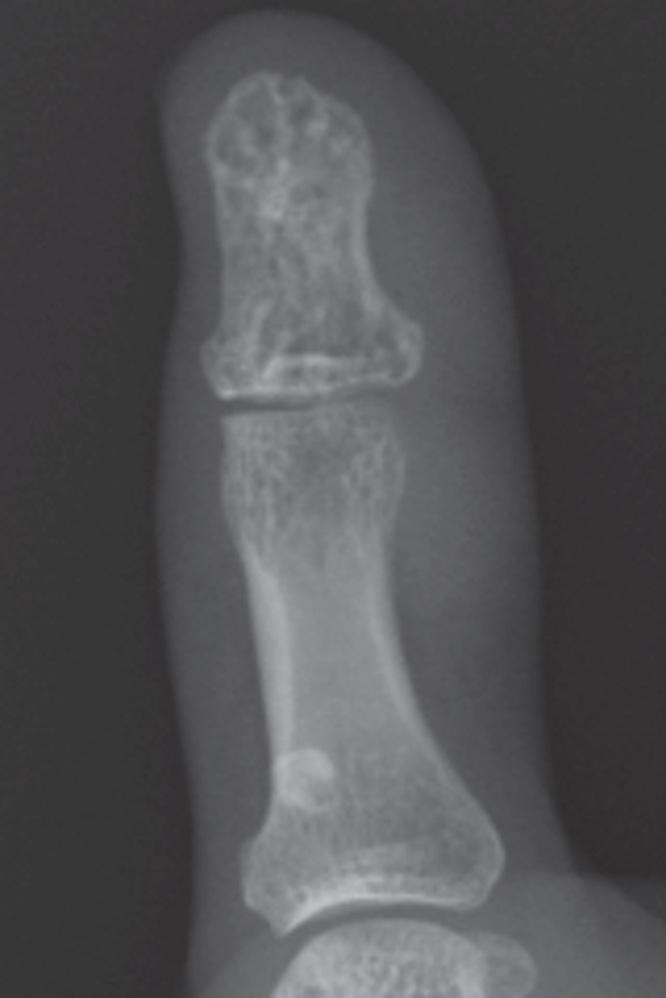

Vascular malformations of bone are complex lesions that can cause deformity and pain. A combined soft tissue and intraosseous venous malformation of the left thumb in a girl was treated with two sessions of ethanol sclerotherapy using a bone marrow aspiration needle under fluoroscopic guidance.

骨血管畸形是一种复杂的病变,可导致畸形和疼痛。一名女孩左拇指的软组织和骨内静脉联合畸形,在透视引导下使用骨髓穿刺针进行了两期乙醇硬化治疗。